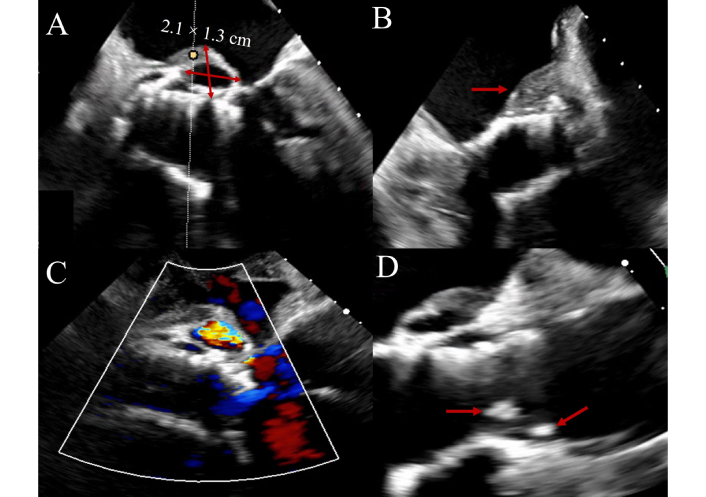

Diagnosing PVE poses additional challenges due to acoustic shadowing and reverberation artifacts from the prosthetic material. These artifacts are particularly problematic in prosthetic valves in the aortic position, whereas in the mitral position, vegetations are often on the atrial side and may be less affected. They can nonetheless obscure vegetations and perivalvular pathology, warranting careful evaluation with adjunctive imaging. Recent data support the utility of three-dimensional TEE, which improves spatial resolution and anatomical clarity, enhancing detection of vegetations and complications [45]. TAVR-IE presents unique imaging difficulties, particularly in early post-implantation periods. The stent frame and associated shadowing complicate visualization, and distinguishing vegetation from pannus or sterile inflammation is often difficult. An illustrative example of TAVR-IE with pseudoaneurysm and leaflet thickening is shown in Figure 3. In these scenarios, multimodal imaging, including PET/CT, is increasingly used to support diagnosis when echocardiography is inconclusive [46, 47].

Transcatheter aortic valve replacement-associated infective endocarditis (TAVR-IE) on transesophageal echocardiography. Figure 3 shows transesophageal echocardiogram imaging of a 77-year-old patient with late-onset TAVR-IE manifesting with vegetations, leaflet thickening and interval development of an aortic root pseudoaneurysm. Panel A: 2.1 cm × 1.3 cm pseudoaneurysm (pulsatile echo-free space with systolic expansion) arising on the posterior aspect of the aortic root with a thickened surface (arrow, Panel B) and with abnormal color Doppler. Panel C: Thickened leaflets with obvious attached vegetations. Panel D: Long-axis view demonstrating communication between the pseudoaneurysm cavity and the left ventricular outflow tract (red arrows) consistent with a contained rupture along the posterior aortic root. The arrows highlight the margins of the pseudoaneurysm neck and adjacent thickened endocardial surface.